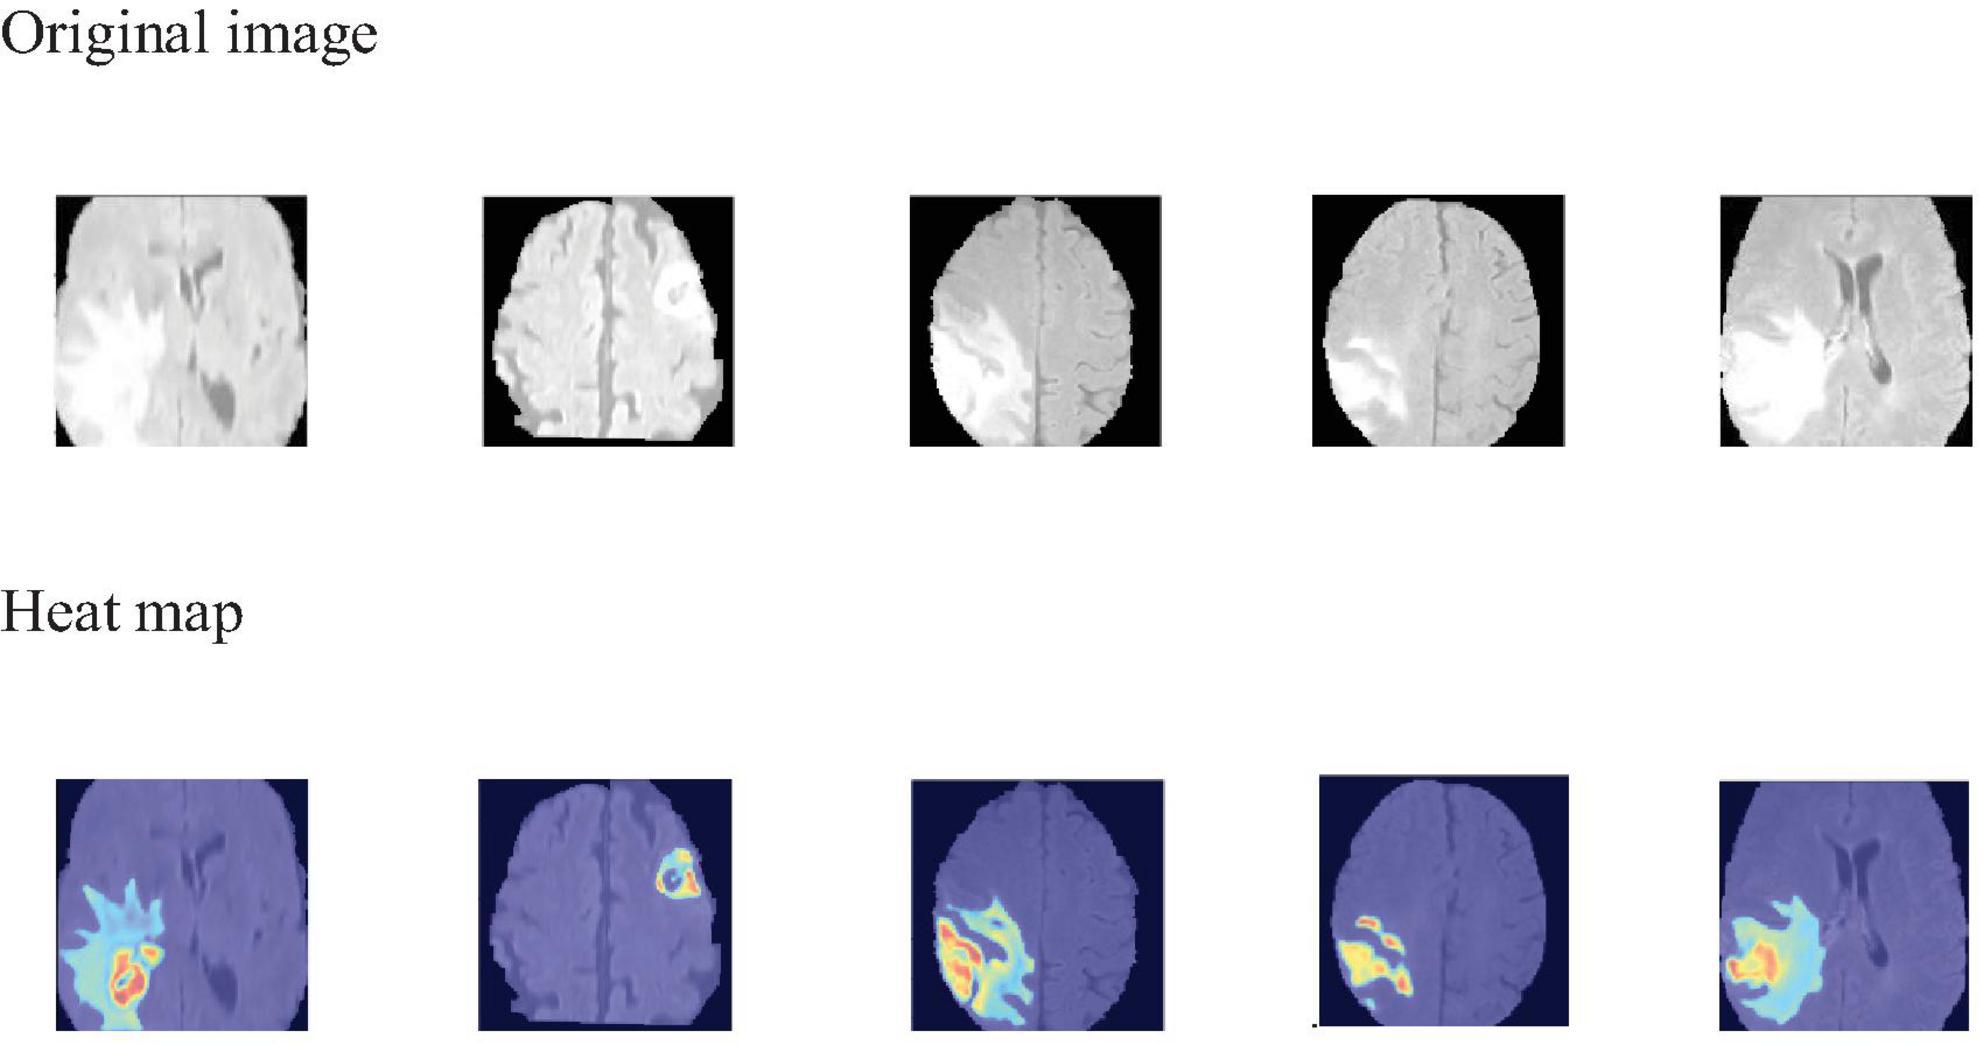

To visually identify the regions of interest on which the model focuses during the 3D brain tumor segmentation process, we employ Grad-CAM (Selvaraju et al., 2019) to generate visual explanations. As shown in Figure 6, the areas highlighted in red and yellow represent the regions that the model pays more attention to, while the blue and darker areas correspond to the regions that the model pays less attention to or receives no attention at all. This visualization technique aids medical professionals by highlighting critical regions within the scan, thereby directing their diagnostic focus and potentially assisting in the diagnostic process.